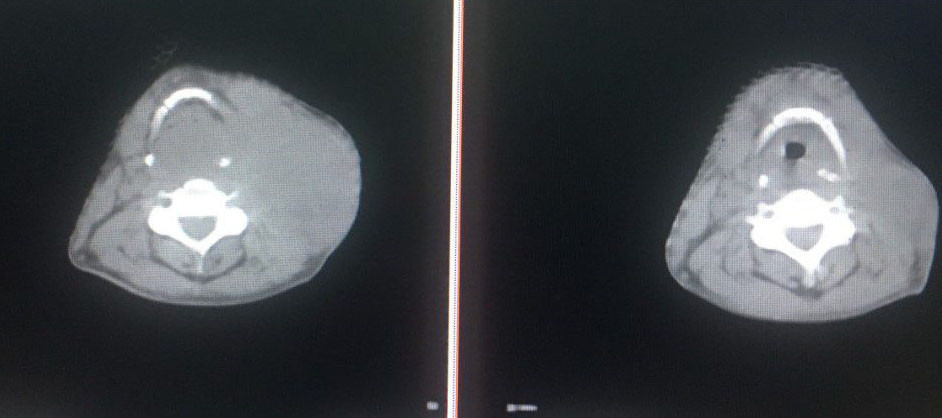

Nghi ngờ bệnh nhân bị sốc đa chấn thương do vỡ các tạng trong ổ bụng, khoa cấp cứu kích hoạt quy trình báo động đỏ nội viện. Kết quả chụp cắt lớp cho thấy bệnh nhân có nhiều dịch máu trong ổ bụng, vỡ lách độ 4, vỡ gan, đụng dập nhiều thành bụng trước.